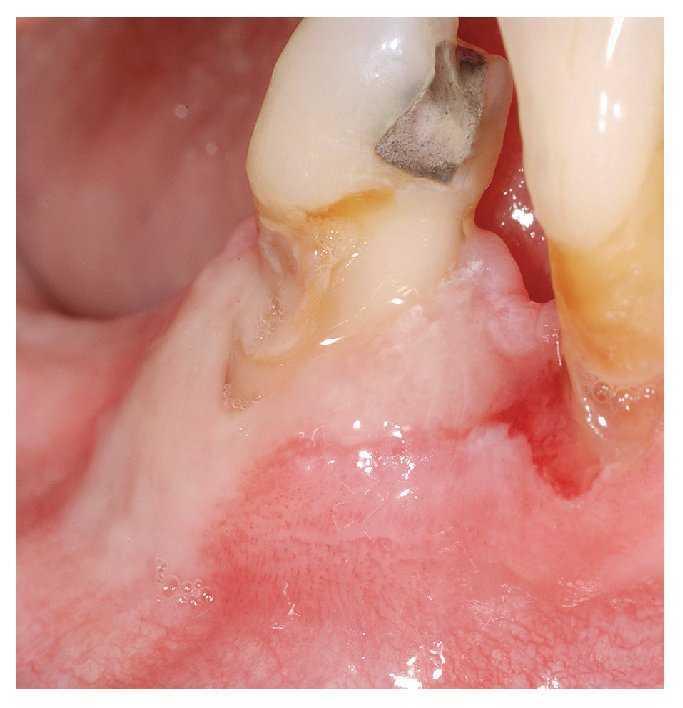

Las aftas son defectos mucosos, redondos u ovalados, circunscritos, dolorosos, de tamaño pequeño (unos pocos milímetros), recubiertos de una capa de fibrina blancoamarillenta y rodeados de un margen eritematoso estrecho (fig. 1). Las aftas pueden aparecer en una o más zonas de la cavidad oral. La aparición simultánea de varias aftas en diferentes áreas de la mucosa oral da lugar a un cuadro denominado estomatitis aftosa. El término «estomatitis aftosa recidivante» (EAR) debe emplearse únicamente en caso de apariciones recidivantes de aftas en la mucosa oral no relacionadas con enfermedades sistémicas.

Figura 1. Afta recubierta de fibrina amarilla y con un margen eritematoso manifiesto en la encía móvil, no queratinizada.

1. Forma menor: aproximadamente el 80% de los pacientes con EAR padecen una forma menor. El afta menor suele tener un diámetro inferior a 5 mm y suele afectar sobre todo a la mucosa móvil, no queratinizada de los labios y las mejillas, del suelo de la boca, del borde lateral de la lengua y de la cara inferior de la lengua (fig. 1). Este tipo de aftas no se suelen encontrar ni en las encías, ni en el dorso de la lengua ni en el paladar. Las lesiones curan en un plazo de 10 a 14 días sin dejar cicatriz.